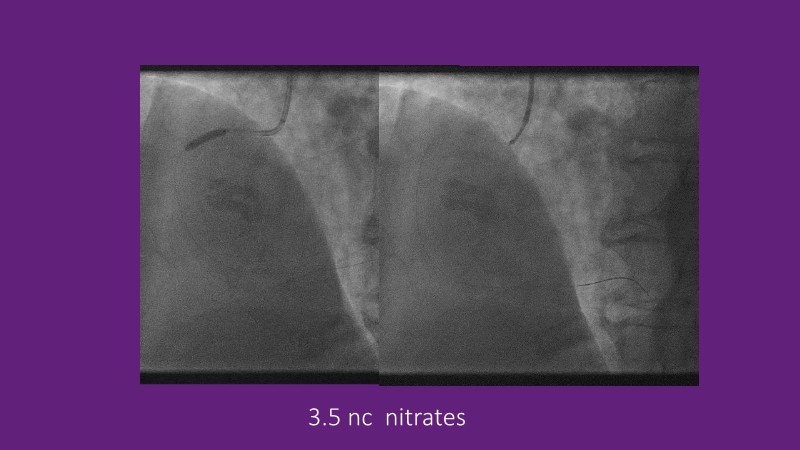

Explore cutting-edge strategies for optimizing drug-coated balloon (DCB) procedures in this session. Uncover practical tips to improve outcomes, review key indications, and examine international consensus on DCB use. Case presentations and expert discussions offer insights to refine your approach.

- To learn the tips and tricks to improve the result with drug coated balloon strategy